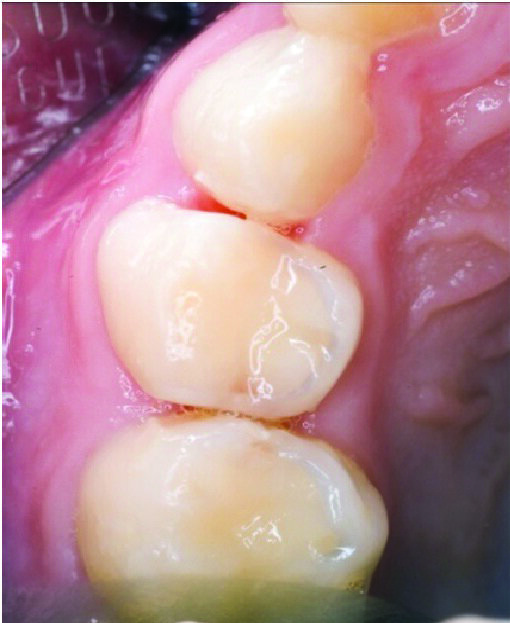

Primary tooth decay management represents a challenge for those who dentally care for children, whether they are general dental practitioners (GDPs) or specialists in paediatric dentistry. For the past 5 decades, the dental literature in the USA and Europe had advocated treating the deep carious primary molar in using the conventional “drill and fill” philosophy. That is, give local anaesthesia (LA) to the child by injection to anaesthetise the tooth, drill the carious tissue out (often after placing a rubber dam-Figure 1) using a high and slow speed drill (Figure 2), restore the primary tooth with a restorative material (often a preformed stainless steel crown or SSC) after carrying out pulp therapy (Figure 3). Although aesthetic crowns are available for primary teeth, they are very expensive and the SSC remains the crown of choice for the carious primary molar (6,7).

Figure 1: The conventional specialist approach: the child having had local anaesthesia and rubber dam placement in preparation for the restoration of 55 which had deep caries into the pulp